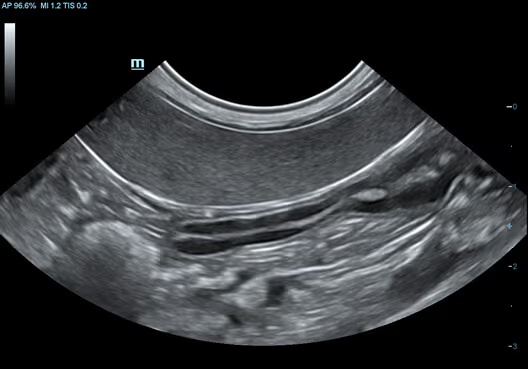

Abdomen, Köpek

Abdomen, Köpek